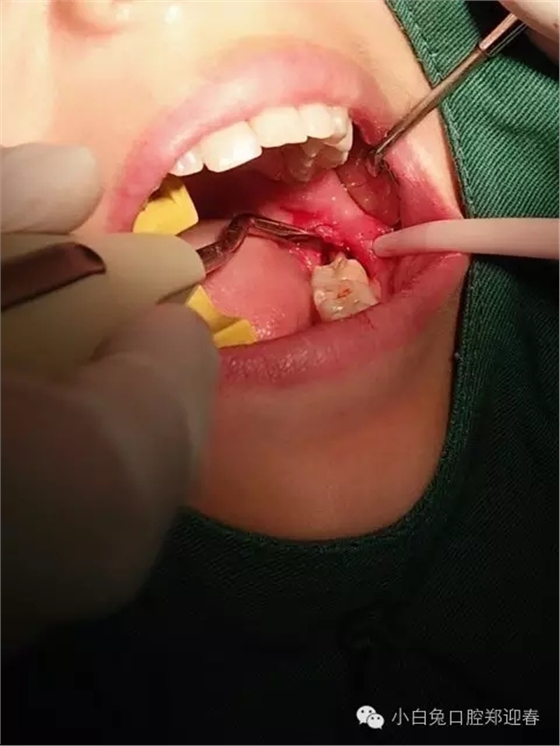

取出第一塊牙根部分,片子顯示依然存在遺留

使用微創(chuàng)理念及方法繼續(xù)拔除剩余部分